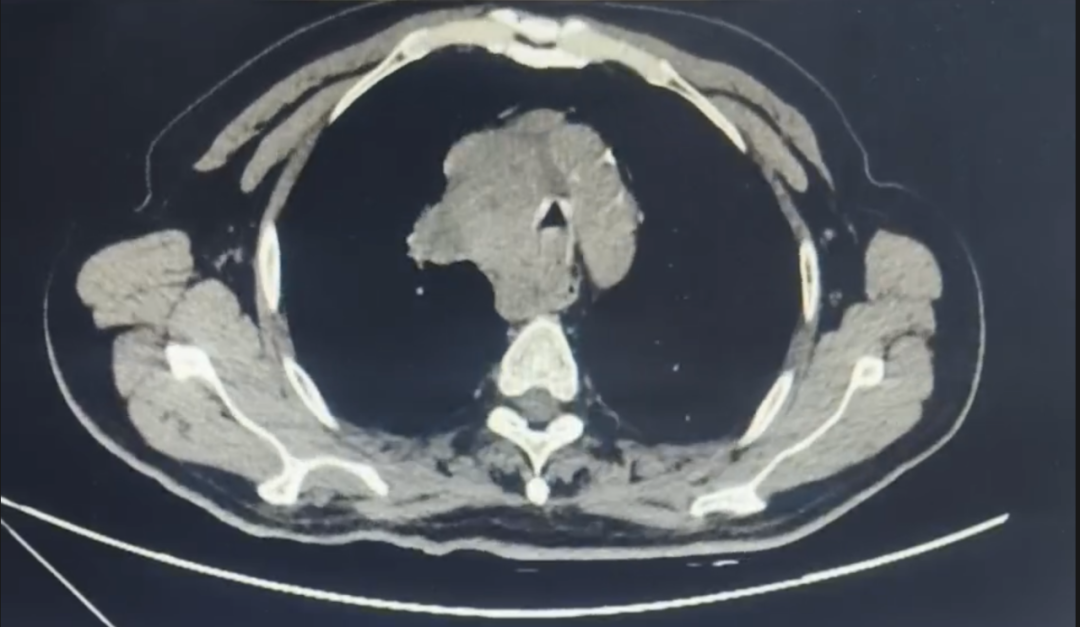

胸部CT增强检查见肿瘤阻塞总气道